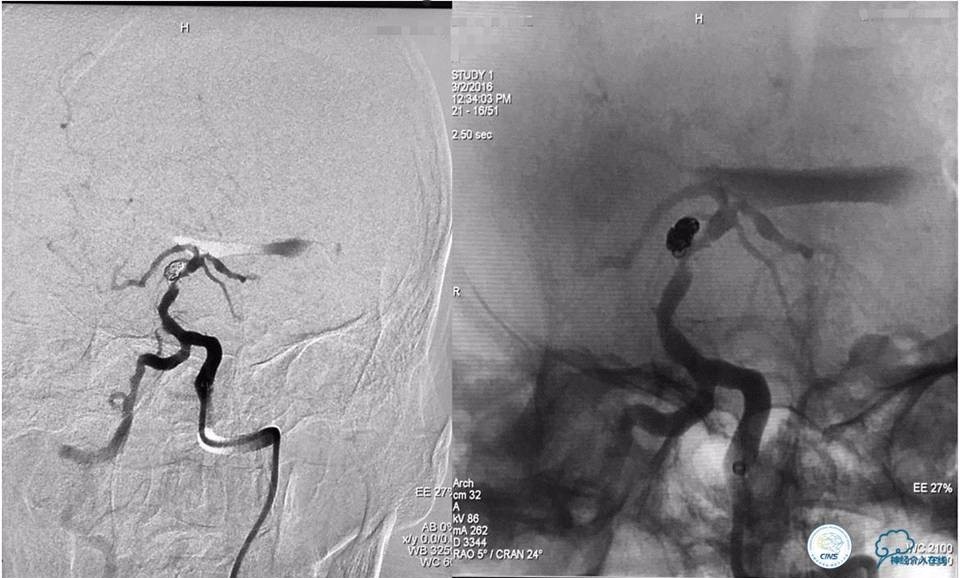

入院后造影检查:

右侧颈内动脉正侧位造影显示:右侧颈内动脉C1段狭窄并溃疡斑块形成,狭窄率约95%,狭窄长度约36mm。

左侧颈内动脉三维旋转后选取工作位角度造影:左侧大脑中动脉分叉部宽颈动脉瘤,大小约8.13mm×7.45mm,瘤颈5.35mm,且上有籽瘤。

血管内治疗策略:右侧颈内动脉开口狭窄处行球囊扩张支架成形术;左侧大脑中动脉分叉部动脉瘤行LVIS JR支架辅助弹簧圈栓塞动脉瘤。

手术过程如下:

(1)球囊扩张+支架成形术

路图下沿导丝送入波科Sterling球囊(直径4mm,长度30mm)至狭窄段,逐渐加压球囊至7atm可见球囊完全扩张,持续3s后迅速抽瘪球囊。沿导丝送入雅培自膨式支架(直径8mm,长度40mm)至狭窄处,准确定位后释放支架。

支架成形术后造影示:支架完全覆盖狭窄段及溃疡斑块,与血管壁贴合良好,残余狭窄率约10%,前向血流较前改善(TICI分级3级)。